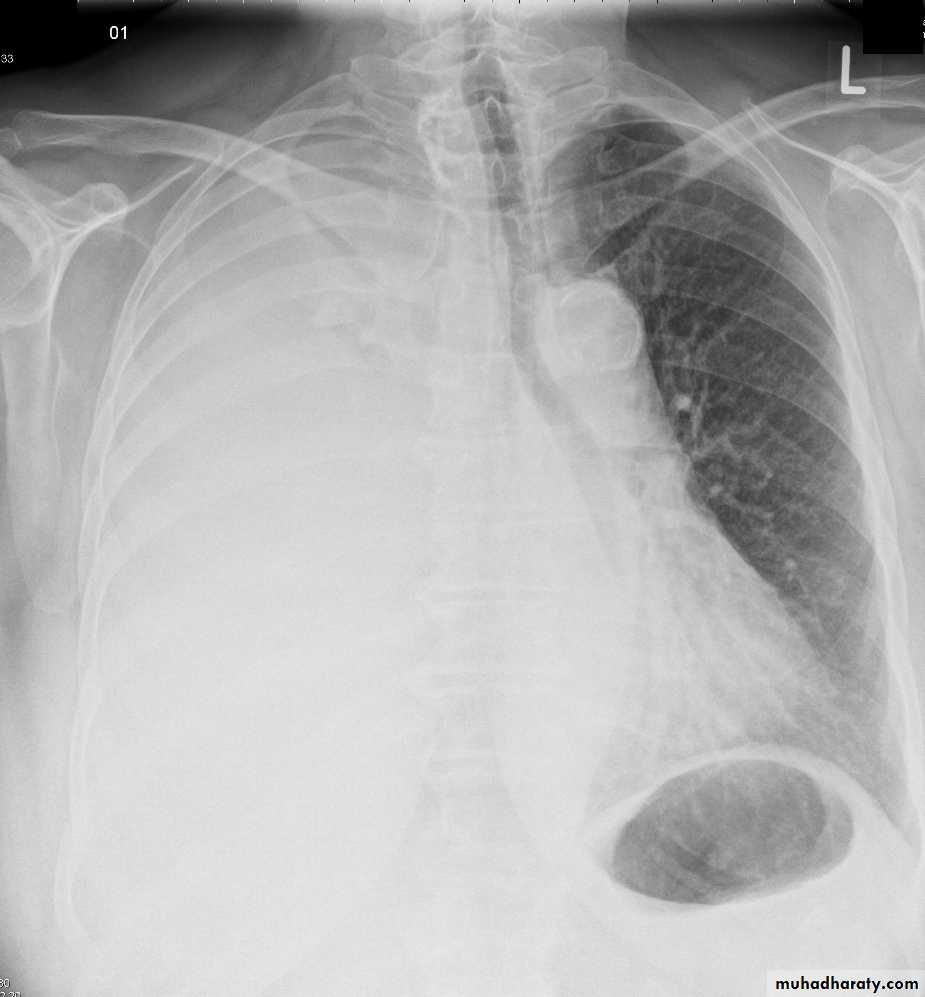

Both PA and AP erect films are insensitive to small amounts of fluid. Features include:

blunting of the costophrenic angle

blunting of the cardiophrenic angle

fluid within the horizontal or oblique fissures

eventually a meniscus will be seen, on frontal films seen laterally and gently sloping medially (note:

A subpulmonic effusion (infrapulmonary effusion) may be seen when there is previously established pulmonary disease, but can also be encountered in normal lungs , They are more common on the right, and usually unilateral

with large volume effusions, mediastinal shift occurs away from the effusion (note: if coexistent collapse dominates then mediastinal shift may occur towards the effusion)